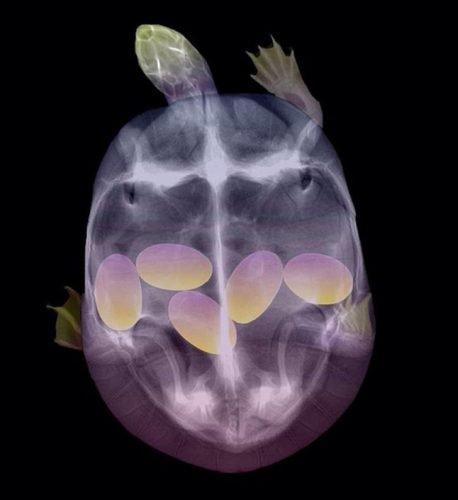

9 - "É legal ter bebês, vão ficar lindas", eles disseram